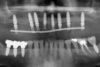

Les 8 implants sont posés et l’armature du bridge provisoire est visible sur le cliché panoramique.

L’ajustage du bridge d’usage sur les piliers est contrôlé sur un cliché panoramique.

Contrôle de l’ajustage du bridge d’usage sur les piliers.